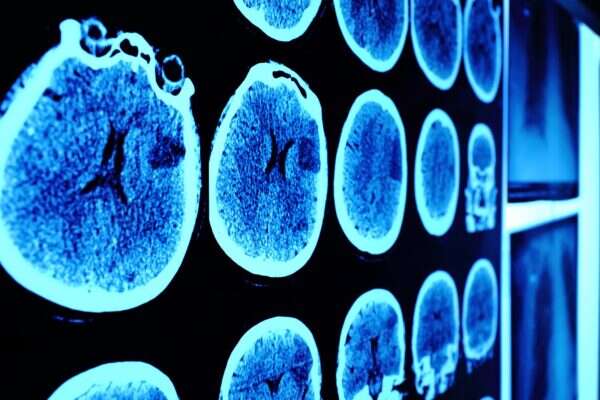

אוון עובד בתחום משנת 1997, הוא היה סורק את מוחות החולים הצמחיים כדי לראות אם הם עדיין בהכרה ומסוגלים להפעיל את מוחם.

המדען אוון סיפר כי מאז המקרה של קייט, "אנחנו סורקים מספר גדל והולך של מטופלים צמחיים כדי למצוא סימני חיים". הראיות מראות כי 15 עד 20 אחוזים מהאנשים במצב צמח בבריטניה, אשר מניחים לגביהם שהם חסרי מודעות - מודעים לחלוטין, למרות שהם אינם מגיבים לגירוי חיצוני.

התפתחות הטכנולוגיה איפשרה למדען המוח לזהות חלקים פעילים במוחו של מטופל בשם סקוט בשנת 2012. המדען סיפר ל"דיילי מייל" כי ביקש מסקוט לדמיין עצמו משחק טניס, וראה באופן ודאי פעילות מוחית אשר מצביעה על הכנת הגוף למכת טניס.